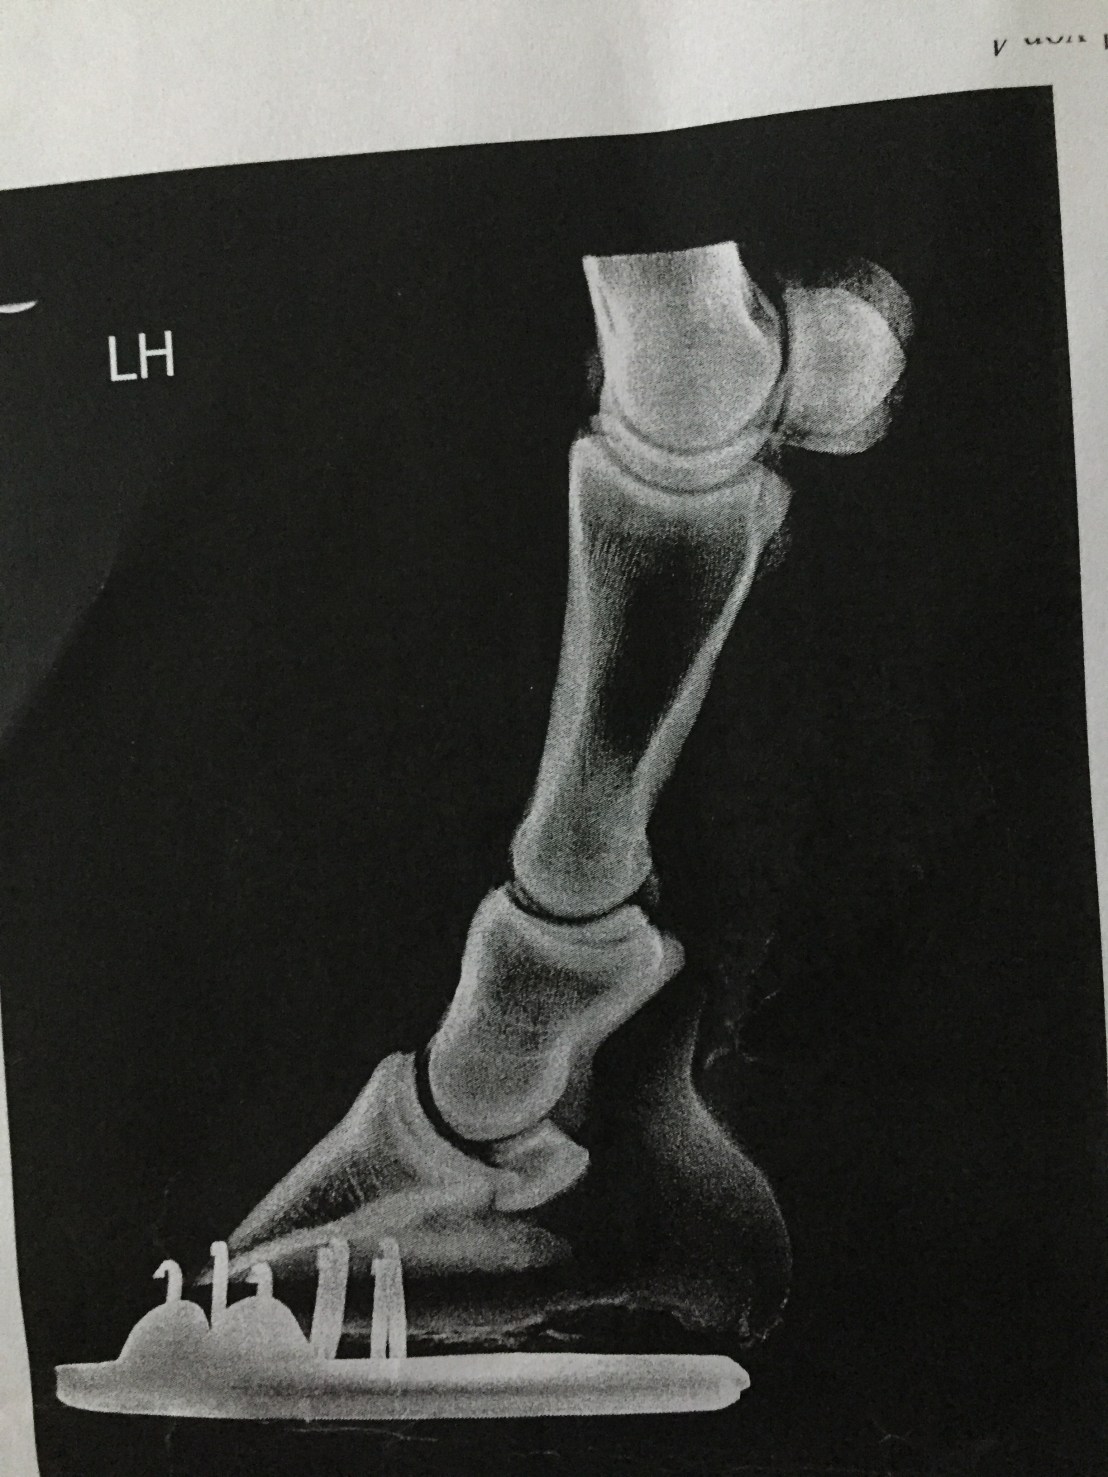

Frank has been on the sick now for two months. Initially he presented with a really sore back back, shoulder and hamstring. I have no idea how he has done this. Two days before the wheel fell off, we came second on a 1m showjumping class -just two seconds behind the winner. This effort was followed by a day off (field turnout) and a steady hack on the second day. On the third day towards the end of a flatwork session practising a couple of Novice tests someone notices his saddle is lifting off his back. Shortly after this Frank stops and cow kicks his belly as if trying to remove a pesky fly and then refuses to move forward- it was like trying to push a wonky shopping trolley. Since he won’t go forward and something is clearly bothering him I dismount feeling sure that there is something wrong with the dressage saddle. I turn him out and Frank has a good roll in the mud and a gallop round the field bucking with glee at being set free. Hmmmmm? he doesn’t look that much in pain does he? Next day he has a day off and on Saturday we box up to a yard with a solarium. He’s still in discomfort Saturday afternoon so we have no choice but to withdraw from Sundays dressage competition and I feel like my world is capsizing. Ten days after Frank’s initial symptoms appeared he has a two hour appointment with Imogen Gifford, physiotherapist. Deep tissue massage, ultrasound and laser therapy to back muscles which appear hard and unyielding. Tuesday appointment with Bethan Lloyd who found similar soreness and realigns a rib. By Friday 25 January he’s no better. The following Monday I make an appointment with Cotts Wednesday 30. As he is trotted up , slight unevenness behind is noted. Lunging in the round pens makes this more obvious. Investigation of hind limb lameness blocked to the left stifle and Frank was prescribed previcox 57mg/day for 30 days then half a tablet for 20 days. Xrays of feet and hocks show no arthritic or bony changes. Both hind xrays show broken back between pedal bone and short pastern – this is being remedied by my farrier who was now able to see exactly what was going on.

This could possibly be affecting Franks stifles. Conservative remedial farriery has reduced this angle by about 3 degrees.